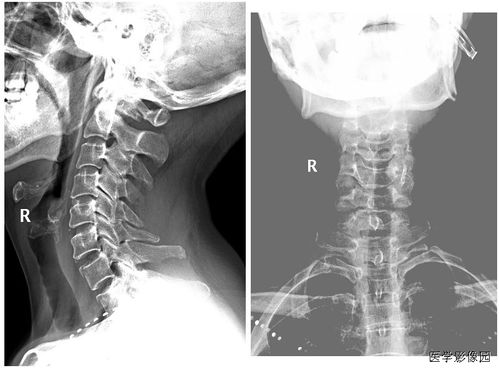

診斷手段:主要是根據(jù)臨床表現(xiàn)加上影像學(xué)檢查診斷。 (1) X線片:凡懷疑骨折者應(yīng)常規(guī)行X線檢查。

可發(fā)現(xiàn)臨床上難以發(fā)現(xiàn)的不完全骨折、深部骨折、關(guān)節(jié)內(nèi)骨折和撕脫骨折,臨床上明確骨折者也應(yīng)行X線檢查明確骨折類型及具體 情況,以指導(dǎo)治療。 (2) CT:對(duì)于骨折不明確但又不能排除者、脊柱骨折可能壓迫脊髓神經(jīng)根者及復(fù)雜骨折者 均應(yīng)行CT檢查。